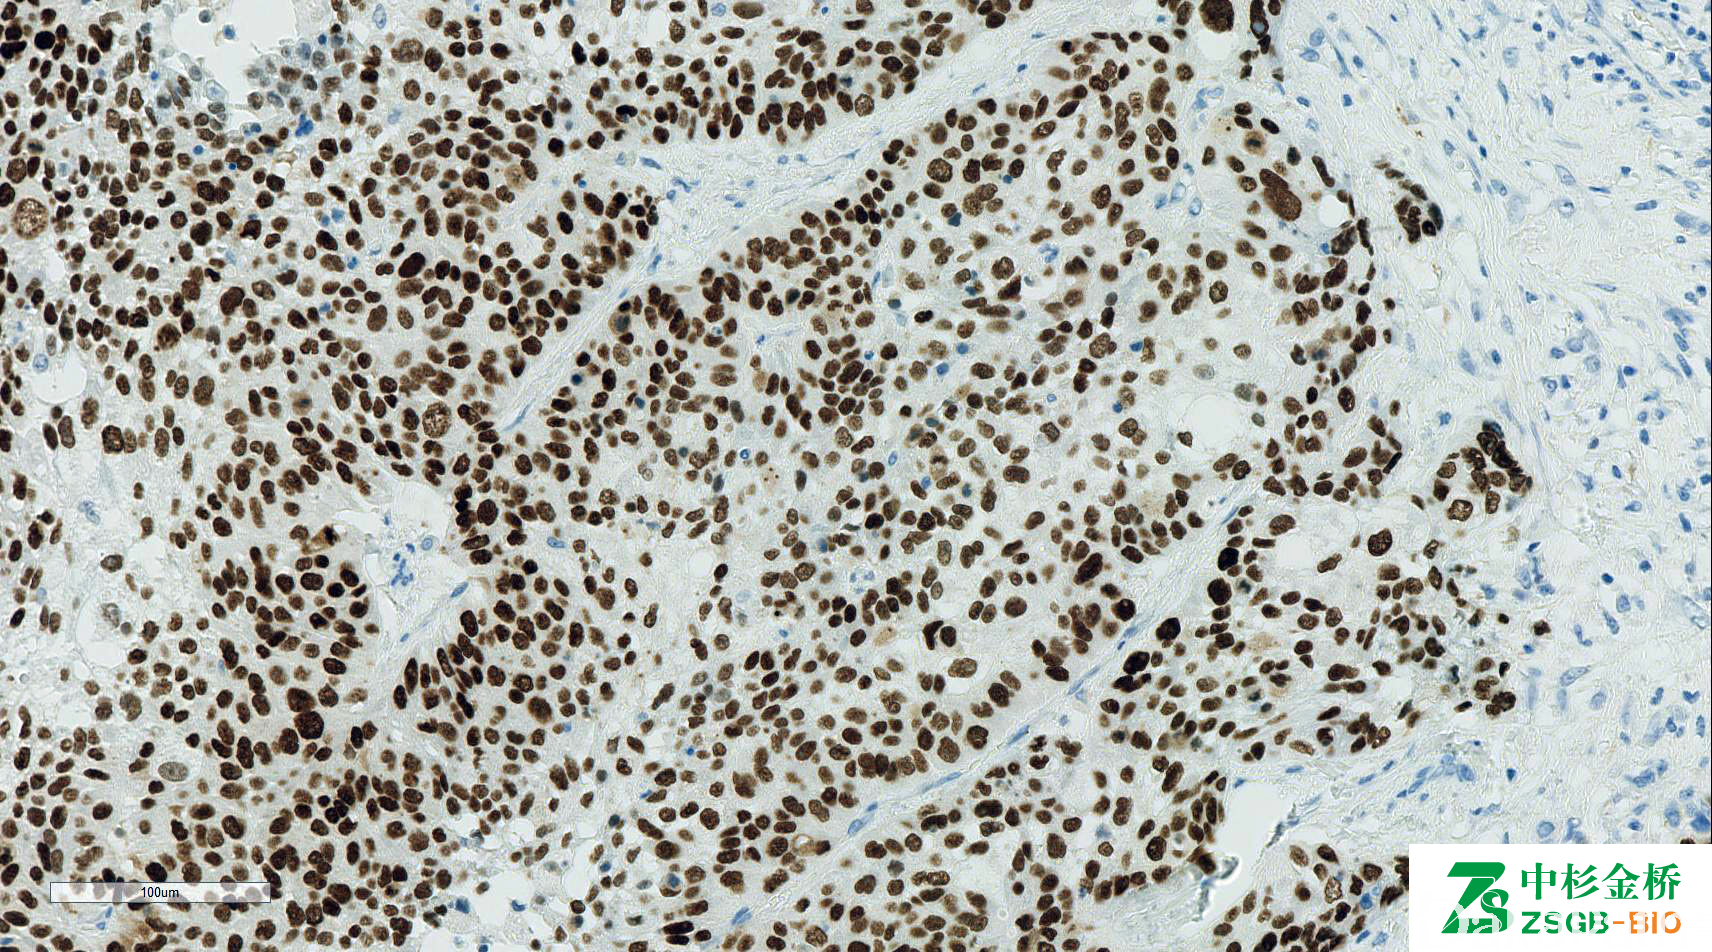

P63

信号定位: 胞核